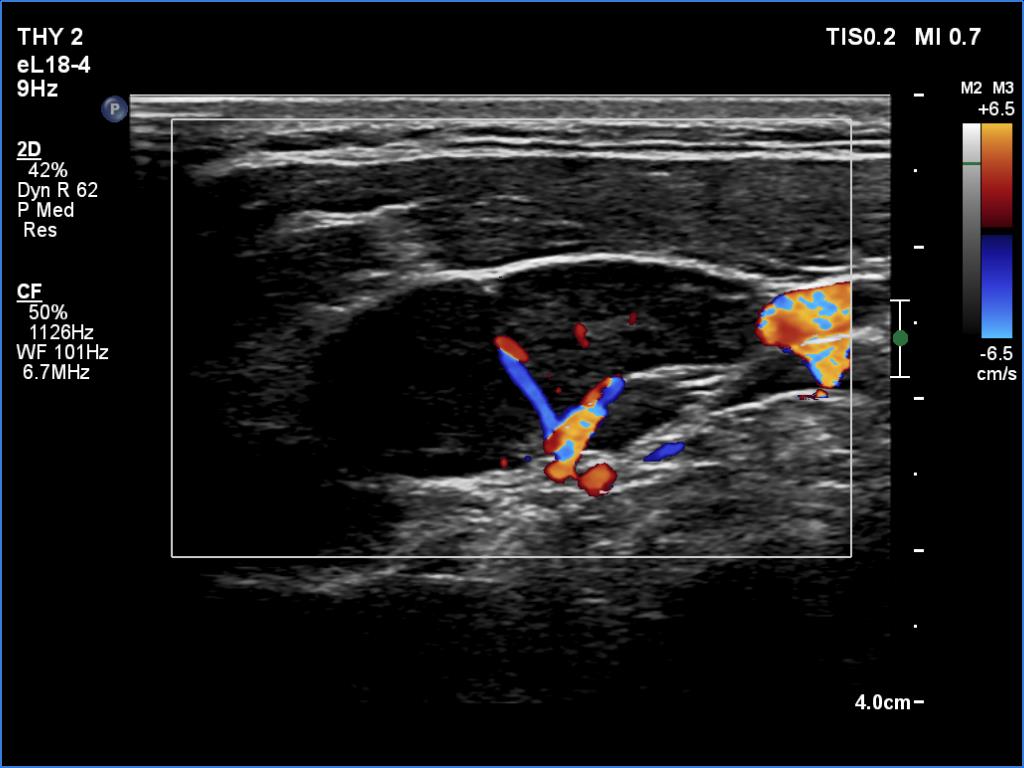

Ultrasonography. The thyroid was echonormal and had multiple minimally/moderately hypoechoic nodules. The lesion in the left lobe was remarkable due to lobulated margins. More than 10 lymph nodes larger than 1 cm in diameter were detected both in the right and the left side of the neck. Some had heterogenous pattern, most of them lacked regular hilum. The vascularity was varied from avascular to obviously irregular.